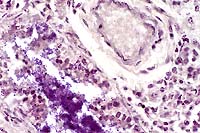

20x

obj

- Case 7-2. Skeletal muscle. Muscle fibers are

hyalinized, fragmented, and have a loss of cross striations,

and are infiltrated and separated by neutrophils, macrophages,

serocellular debris.